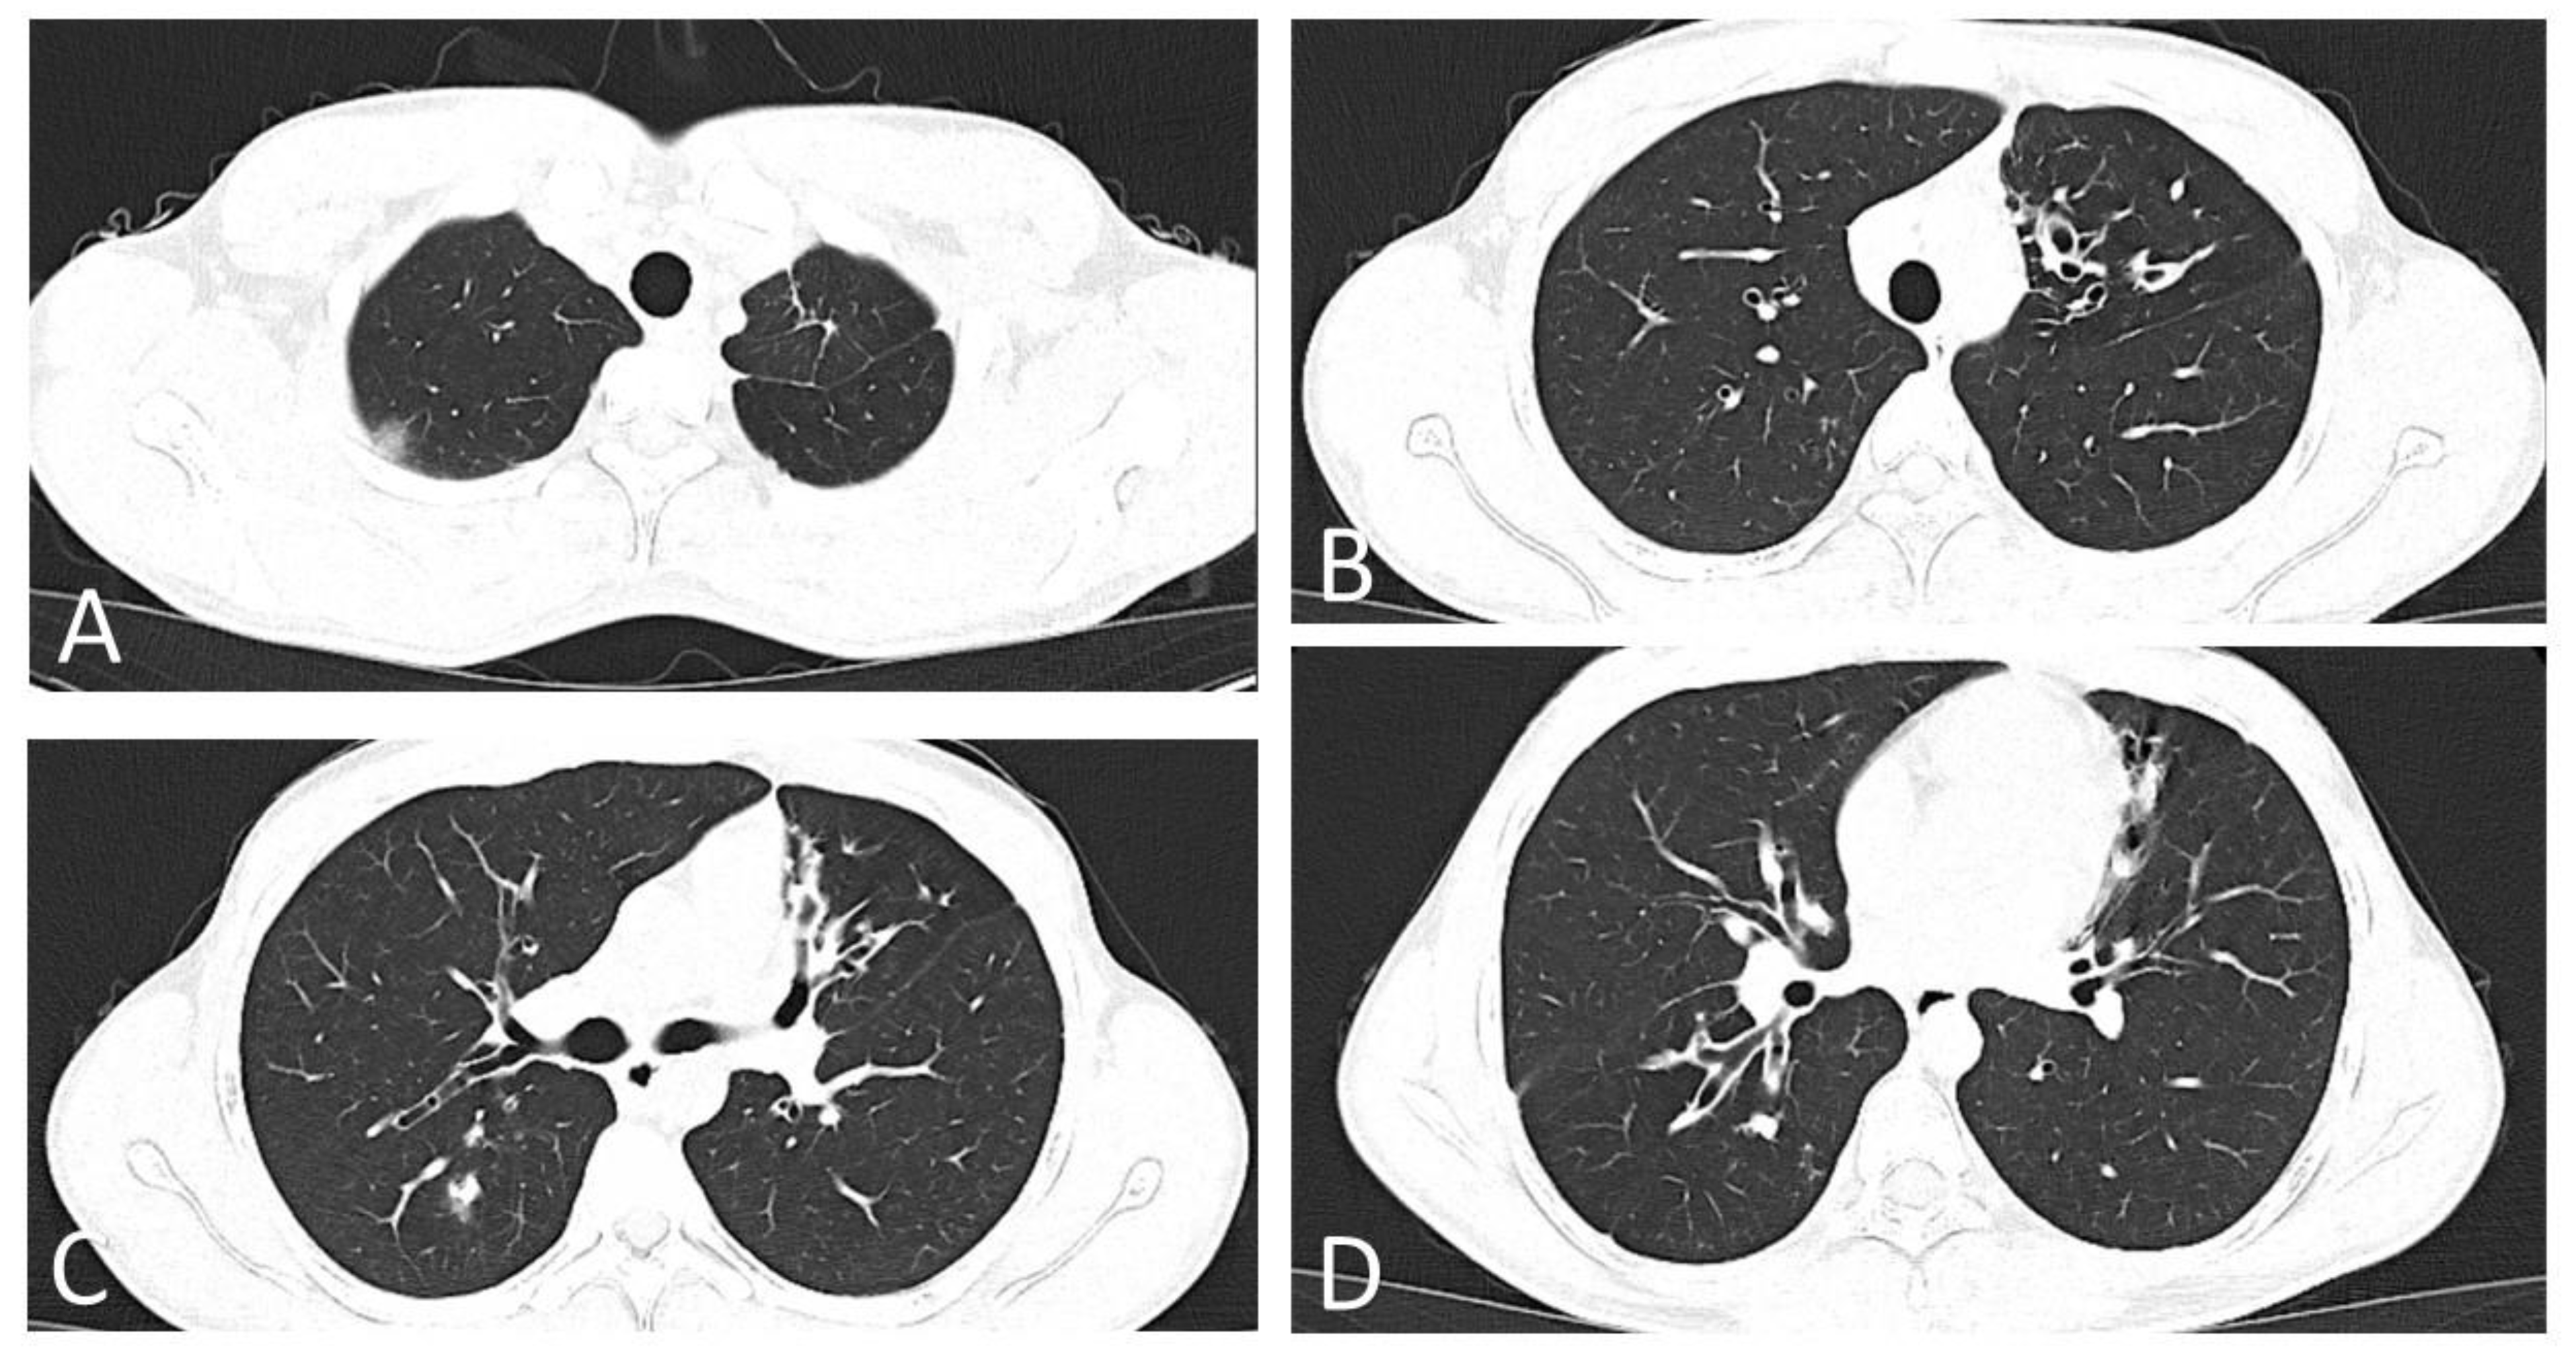

Immediately after confirmation of COVID-19, the patient was referred to Infectious Diseases for evaluation and staging of the disease. At the time of assessment, the patient was afebrile (36.6 °C), with blood pressure 121/78 mmHg, heart rate 85 bpm, respiratory rate 20 breaths/min and SpO2 = 97% in ambient air. The electrocardiogram showed no pathological changes (sinus rhythm, PR interval = 138 ms, QRS duration = 76 ms, QT/QTc = 354/421 ms). A native computed tomography of the chest was performed, and it revealed isolated central and peripheral ground glass opacities distributed bilaterally, suggestive for mild COVID-19 pneumonia, on a background of bilateral bronchiectasis and fibrotic-like densities in the left lung apex (Figure 2 and Supplementary Materials).

Figure 2. Native chest CT images on the sixth day of disease. (A) Native chest CT scan, lung window, apical section: subpleural ground glass opacity in the dorsal segment of the right upper lobe, suggestive for COVID-19. Linear densifications in the anterior segment of the left upper lobe, suggestive for fibrotic sequelae due to the patient’s underlying disease. (B) Native chest CT scan, lung window, aortic cross section: clustered cylindrical bronchiectasis in the lingula. (C) Native chest CT scan, lung window, hilum section: multiple cylindrical bronchiectasis in the lingula and middle lobe. Pseudonodular condensation area, with ground glass halo, in the right Fowler segment. (D) Native chest CT scan, lung window, infrahilar section: multiple cylindrical bronchiectasis in the right Fowler segment, in the anterior segment of the left upper lobe and the superior lingular segment. Pseudonodular condensation area, in the right Fowler segment.